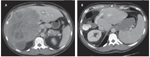

FIGURE 3

Representative abdominal CT scan of a 48-year-old-man with isolated metastatic melanoma of unknown primary

It would be easy to be nihilistic if not for the real prospect of long-term survival seen in practices where aggressive approaches are taken. Although the analogy is imperfect, the concept of “variable interval reinforcements” is likely operative in such practices, with the occasional successes reinforcing enthusiasm for aggressive treatments. Figure 3 depicts one example of such a success-a 48-year-old male who presented to our institution for the treatment of metastatic melanoma. The patient initially presented with fatigue and anemia (hemoglobin level of 3.5 g/dL). Colonoscopy revealed an ileal lesion with biopsy-proven melanoma of unknown primary. Evaluation included a computed tomography (CT)/positron emission tomography (PET) scan, which identified an additional lesion in the liver. The patient underwent a small bowel resection from which he recovered unremarkably; he then started interleukin-2 therapy. Two years later he developed rapid progression of disease isolated to the right liver and was at that time referred for possible liver resection. The patient underwent an uneventful right hepatectomy and is currently disease free 6 years later.